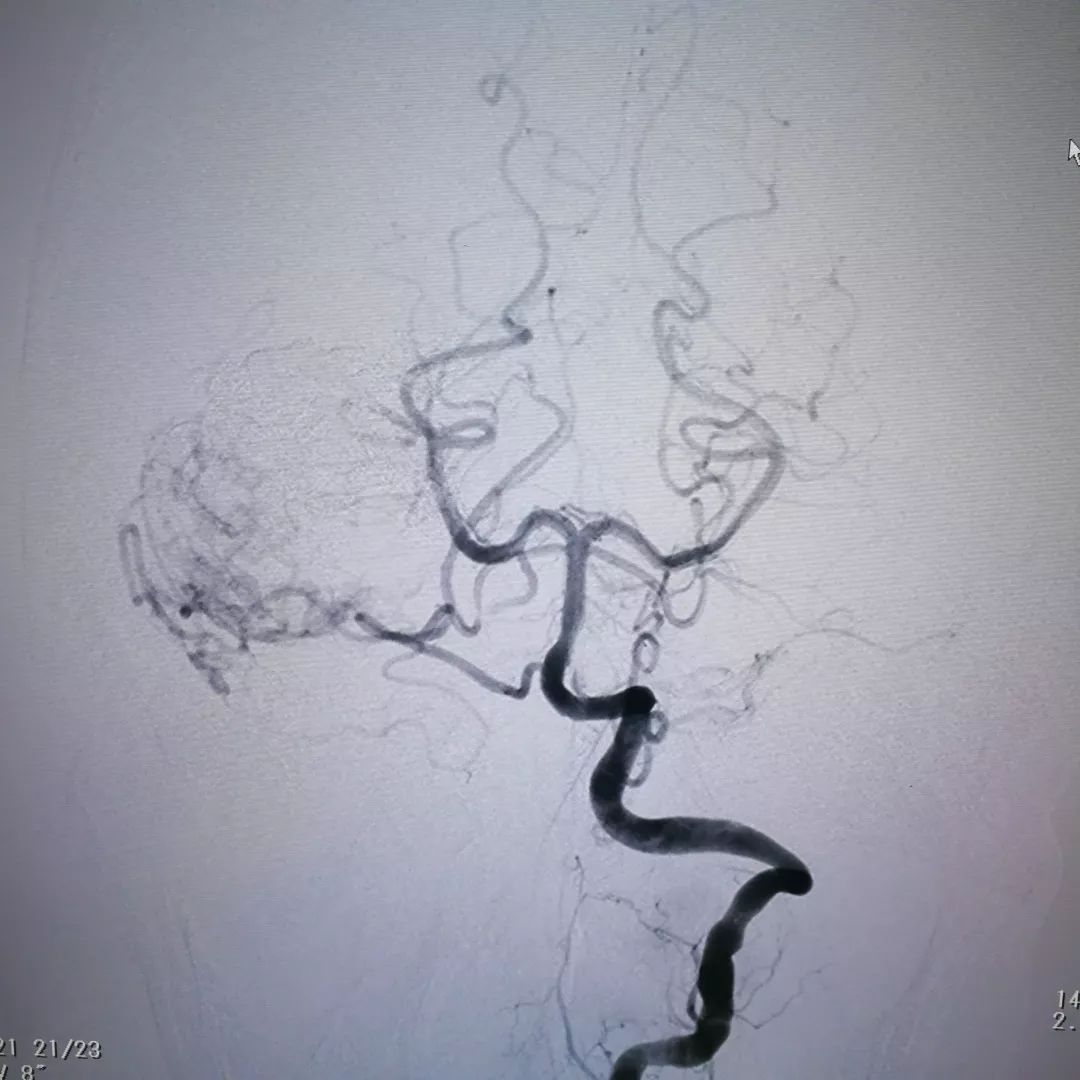

脑血管造影证实肿瘤血供极其丰富,血窦样结构充满血液,供血动脉粗大

复查造影提示肿瘤内大部分血窦被堵塞,肿瘤内血液供应明显减少,从而达到降低手术风险减少术后并发症的目的